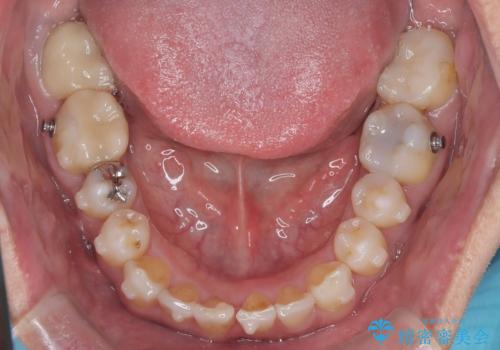

- 「八重歯と歯のでこぼこを治したい」を主訴に来院された患者様です。

歯は抜かずに奥歯の遠心移動とIPRで八重歯とでこぼこを改善しました。

左上3番は保険治療(CR)の劣化による二次カリエスになっていますので、後日治療予定です。